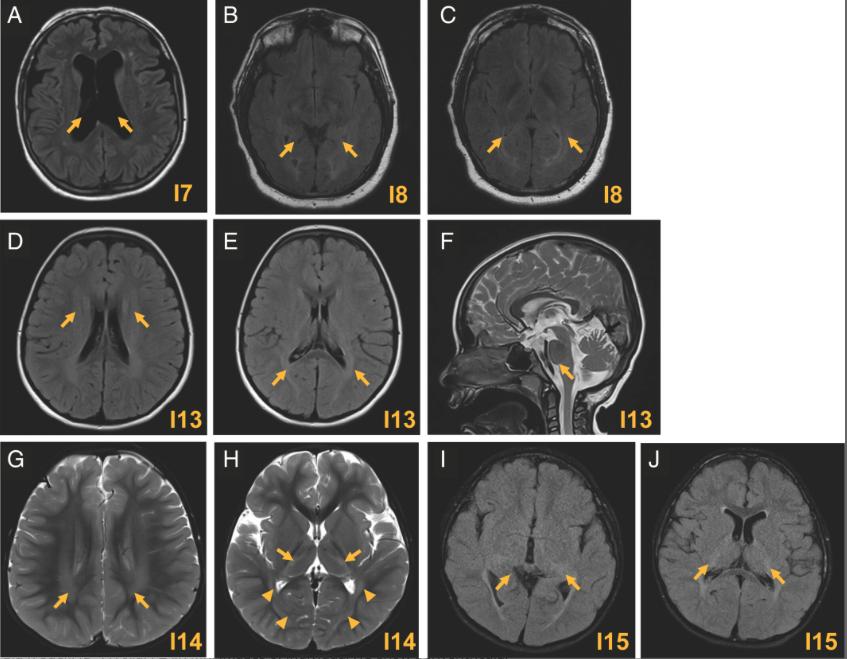

Figure 2. Cerebral MRI from individuals carrying the p.(Ala363Val), the p.(Asn369Ser), and the p.(Glu478del) variants. (A) Axial FLAIR MRI image from individual I7 show atrophy and an increase of ventricular spaces (arrows). Individual I7 carries the p.(Ala363Val) variant. (B, C) Axial brain MRI images show mild T2 signal changes in the periventricular white matter posteriorly in individual I8, carrying the p.(Asn369Ser) variant. (DH) Axial MRI scans of individuals carrying the p.(Glu478del). (DF) Axial FLAIR MRI images of individual I13 show periventricular white matter abnormalities. (F) Sagittal T2-weighted image shows superior vermis atrophy (arrow C). (G, H) Axial T2-weighted image through the centrum semiovale of individual I14 demonstrates a hyperintense signal involving the periventricular white matter with posterior predominance (arrows D). T2-weighted signal hyperintensity is also present in the ventrolateral thalami (E arrows), as well as the optic radiations and subcortical occipital white matter (E arrow heads). (J, K) Axial T2-weight images demonstrate posterior mild diffuse periventricular hyperintensity signal abnormality that extended into the posterior capsule into the thalami bilaterally in individual I15. FLAIR=fluid-attenuated inversion recovery; MRI=magnetic resonance imaging.

[Color figure can be viewed at www.annalsofneurology.org] |